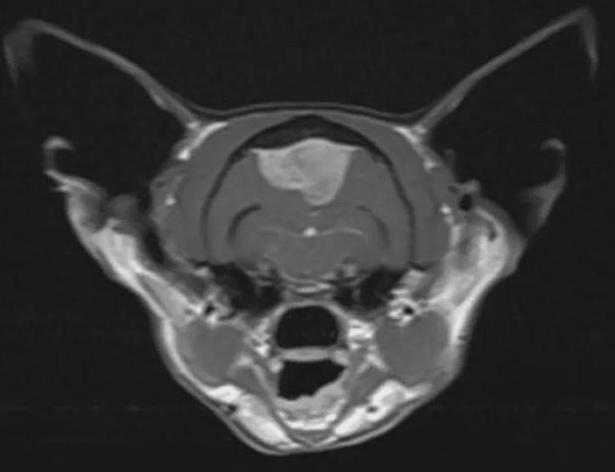

亨利是一只家养短毛猫,今年7岁。一段时间以来,它的主人玛吉吉布发现它不怎么吃东西,而且精神状态日渐萎靡,总是昏昏欲睡。由于担心亨利的健康状况不断恶化,便把它送到了布里斯托尔的兽医专家那里,动物医院的顶级神经学家迅速对它进行了检查。在亨利的核磁共振扫描影像上显示,它的颅内有一个很大的肿块,或许这就是导致它现在这种状态的原因所在。

亨利立即被送往手术室,一组外科医生和护士为它进行了“开颅手术”,手术切除了它的部分头骨,成功地切除了麻烦的脑膜瘤。然后,一个尖端的钛合金网被用来重建亨利的头部,成为了它头骨的一部分。据悉,这次细致而精确的手术持续了两个多小时,对肿瘤进行病理分析后,确认这个肿瘤是良性的。